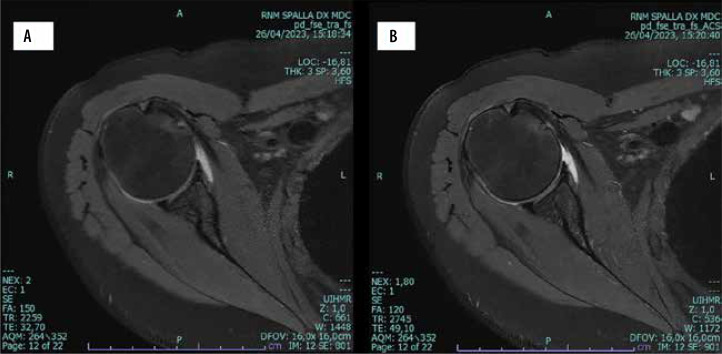

Magnetic resonance imaging (MRI) is a powerful imaging modality, but one of its drawbacks is its relatively long scanning time to acquire high-resolution images. Reducing the scanning time has become a critical area of focus in MRI, aiming to enhance patient comfort, reduce motion artifacts, and increase MRI throughput. In the past 5 years, artificial intelligence (AI)-based algorithms, particularly deep learning models, have been developed to reconstruct high-resolution images from significantly fewer data points. These new techniques significantly enhance MRI efficiency, improve patient comfort and lower patient motion artifacts. Improving MRI throughput with lower scanning duration increases accessibility, potentially reducing the need for additional MRI machines and associated costs. Several fields can benefit from shortened protocols, especially for routine exams. In oncologic imaging, faster MRI scans can facilitate more regular monitoring of cancer patients. In patients suffering from neurological disorders, rapid brain imaging can aid in the quick assessment of conditions like stroke, multiple sclerosis, and epilepsy, improving patient outcomes. In chronic inflammatory disease, faster imaging may help in reducing the interval between imaging to better check therapy outcomes. Additionally, reducing scanning time could effectively help MRI to play a role in emergency medicine and acute conditions such as trauma or acute ischaemic stroke. The purpose of this paper is to describe and discuss the advantages and disadvantages of introducing deep learning reconstruction techniques to reduce MRI scanning times in clinical practice.